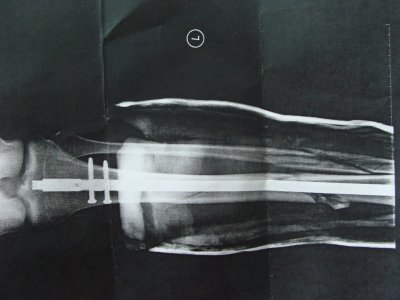

Меня отправили в госпиталь, там сразу же в этот день через пару часов назначили операцию. В ходе операции мне вв большую берцовую кость вставили титановую спицу, которую закрепили двумя шурупами сверху и одним снизу. Малую берцовую кость "собрали в кучу". Извините, не владею медицинской терминологией. Вобщем вот и результат операции

DSC01525.JPG